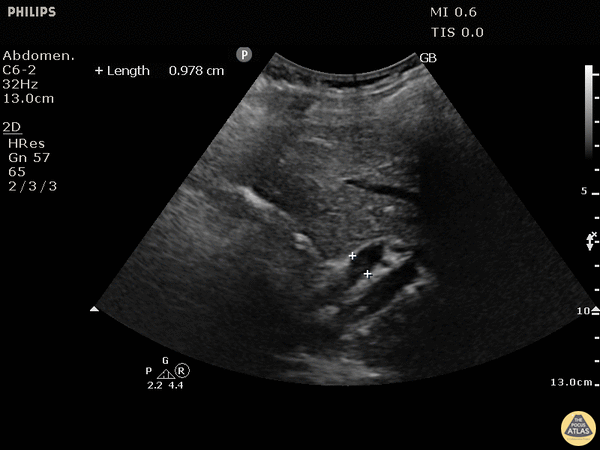

Biliary - Dilated Common Bile Duct

This patient has a dilated common bile duct and obstructive pattern LFTs, highly suggestive of choledocholithiasis or other biliary obstruction. No stone is visualized on this study. A normal common bile duct should be <4mm plus 1mm per decade after 40 years of age. Here it is 9.78 mm. POCUS is highly sensitive for acute cholecystitis but as many people already know, it can be hard to find the CBD, which is reflected in the lower sensitivity and specificity for this indication in many studies. Justin Bowra MBBS, FACEM, CCPU Emergency Physician, RNSH et al. (Dr. Ken Lee)